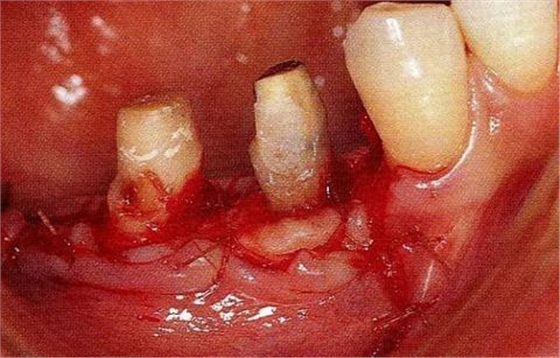

病例4維系鄰牙的骨水平的戰(zhàn)略性拔牙:

圖17-1 ( 左 ),2 ( 右 )▲右下4近中9mm的骨緣下缺損,兩側(cè)全口橋體修復(fù),但是這顆患牙保留的情況下會影響牙列的維持,鄰接牙的骨水平在較高的位置,拔牙后可以獲得平坦的骨水平。即使是右下4嘗試再生療法,假說可以100%的成功,右下3遠(yuǎn)中骨水平也會形成3mm以上的臺階。而且再生治療也需要患者登上1年半以上的時間。所以最終選擇拔牙的處理。